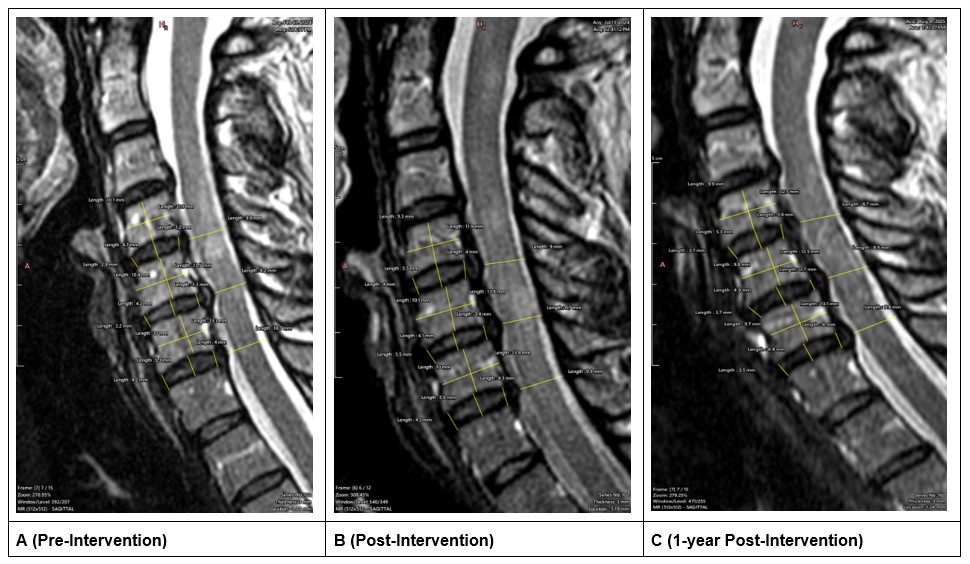

The average disc height ([Anterior Disc Height + Middle Disc Height + Posterior Disc Height]/3) at the C5–C6 level increased from 3.61 mm before treatment to 3.66 mm after treatment (+0.05mm; 1% increase; Figures 5A and 5B). At 1 year follow-up, the disc height continued to increase an additional 0.12 mm resulting in an overall increase of 0.17 mm (5% increase; Figures 5A and 5C).

Figure 5. Longitudinal measurements of the mid-sagittal slices. A (pre-treatment), B (post-treatment), C (1 year follow-up).

The ratio of disc height to AP diameter of the overlying vertebrae at the C5–C6 level stayed consistent at 0.27 before treatment and 0.27 after treatment (Figures 5A and 5B). However, at 1-year follow-up, this ratio increased by 0.03 to a final value of 0.30 (11% increase; Figures 5A and 5C). Additionally, the ratio of disc height to height of the overlying vertebrate increased from 0.35 before treatment to 0.36 (3% increase) after treatment and 0.38 (9% increase) at 1 year follow-up. Additional measurements of the adjacent vertebral levels (C4–C5 and C6–C7) are provided in Table 2.